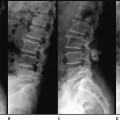

30 Dynamic posterior stabilization is now a popular form of surgical intervention employing a highly diverse range of devices. These devices are designed to relieve several different pathological conditions, including spinal stenosis and diskogenic pain, by fulfilling a range of biomechanical functions. The purpose of this chapter is not to describe individual devices in great detail or to evaluate their clinical effectiveness in different applications because this will be covered in subsequent chapters. The proposed biomechanical actions of these devices will be analyzed in generic terms so that the reader develops an understanding of the fundamental principles involved in their usage. Simplistically, dynamic posterior stabilization devices have the potential for affecting the spine in several ways: The extent to which a given device achieves any or all of the foregoing depends upon its design and mode of action and also on the mechanics of the segment that is treated. Posterior stabilization devices fall within two broad categories of design: interspinous process spacers and pedicle screw–based systems. Interspinous spacers have the potential to cause the segment to flex, distract the disk space, block extension, unload the disk, and subtly change loading and motion patterns in extension. Those that have additional tension bands, such as the Wallis Mechanical Normalization System (Abbott Spine, Inc., Austin, TX), also have the potential to limit flexion and modify flexional loading and motion patterns. Pedicle screw based–systems have the potential to modify the full range of segment behavior. The extent to which these potentials can be achieved is discussed in the remainder of this chapter. All posterior stabilization devices have the potential to increase the flexion or extension angle of the unloaded segment. The degree to which they do this, or indeed if they do it at all, depends on the size of the device relative to the separation of the pedicle screws or spinous processes. For example, if the spacer height of a Dynesys Dynamic Stabilization System (Zimmer Spine, Inc., Warsaw, IN) is greater than the separation of the pedicle screws in the neutral position, the segment will be forced into flexion, whereas if they are shorter it will be forced into extension. Tension band–only devices, such as the Graf Ligament System (Neoligaments, Leeds, U.K.), will force the segment into extension, the degree of angulation being dependent upon the tension in the ligament. This ability comes from the fact that the posteriorly positioned device can apply a bending moment to the segment. Motion segments have a highly nonlinear bending moment versus bending angle relationship where, close to the neutral position, small applied bending moments result in large, angular displacements (Fig. 30–1). It is therefore relatively easy for a device to apply a bending moment that is sufficient to alter the angulation of the segment. It should be noted that in more complex devices such as the Dynesys, the relationship between spacer length and flexion-extension angle is complicated by the application of tension through the cord, which results in postimplantation deformation of the spacer. For example, application of the standard tension to the cord of a Dynesys device will result in a 2 mm shortening of the spacer. Such deformation must be taken into account if it is wished to control the flexion-extension angle of the segment using the device. Study of Fig. 30–1 indicates why it is very difficult to use a posterior stabilization device to change the neutral position disk height of a segment (i.e., to apply distraction). Clearly it is possible to apply many devices in such a way as to apply a distractive force either to the spinous processes or the pedicles. Such a force is, however, applied posteriorly to the ICR of the segment and will therefore also apply a bending moment. This bending moment is greater for a given distractive force the more posteriorly the device is mounted. From Fig. 30–1 we can see that from the neutral position (the origin of the graph) comparatively small moments are required to cause relatively large changes of angulation. However, the intervertebral disk is very stiff (~2 kN/mm) in the axial direction. Very large forces must therefore be applied to achieve small amounts of distraction. Hence, application of distraction forces using posterior stabilization devices will result in flexion rather than distraction. The only circumstance under which this is not the case is if the stabilization device is itself very stiff to bending. It will then be able to apply an opposing bending moment to the segment that will prevent it from flexing. However, such rigid fixation devices by definition do not stabilize dynamically; they will prevent any form of bending to the segment. It is possible for a device to prevent loss of disk height, particularly in extension. Consider, for example, the X-STOP Interspinous Process Decompression system (St. Francis Medical Technologies, Inc., Alameda, CA), which provides no rigidity in flexion, but which becomes very stiff in extension when the spinous processes come into contact with the titanium spacer. In this case the ICR will move posteriorly, attracted to the point of maximum stiffness (see later for a detailed explanation). The segment will then rotate about the device (Fig. 30–2) maintaining vertebral canal width and distracting the disk. This is an example of a device with low stiffness in some situations (allowing motion) and high stiffness in others (preventing motion). Figure 30–1 A typical bending moment versus flexion angle for a motion segment. Note the neutral zone where small changes in bending moment result in large changes of angle. Control of sagittal plane bending has been the primary design criterion for the majority of dynamic stabilization devices. The degree to which they achieve this, and under what circumstances, is more fully described in the device-specific chapters. The fundamental principles by which they operate is discussed in this chapter.